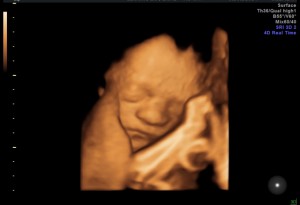

At your last ultrasound, the technician surprised us by showing us a 4D view of you – and boom! There you were! First thing your mom said was, “He has your nose!” And I’m sorry for that. Haha! (not really) I must say, though, I was kind of hoping you would have your momma’s nose. But really, in the end, who cares? You are absolutely ADORABLE! You are going to be here before we know it, and more likely – before we’re ready.